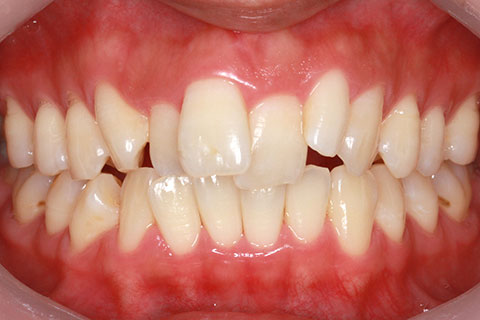

ハーフリンガル矯正3:上の歯のみ舌側矯正で治療(矯正期間24ヶ月)

治療前

治療中(開始直後)

治療中(開始半年後)

治療後

- 年齢・性別

- 25歳女性

- 治療期間

- 2年0ヶ月

- 抜歯

- 上下4番抜歯

- 治療費

- 110万円

- 治療内容

- 施術の副作用(リスク)

- 表側矯正と比較して、力学的な操作性が複雑なため、ボーイングエフェクトを起こしやすい。